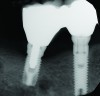

This assessment presumed patients were healthy. However, there are situations that can contribute to bone loss and individuals may experience a greater amount of osseous resorption than reported in this evaluation: systemic conditions (eg, diabetes, osteoporosis); smoking; medications (eg, bisphosphonates)90,91; subgingival cement retention92 and peri-implantitis; and in some patients, time appears to be a factor (Figure 16 and Figure 17).93 Furthermore, there are patients that lose more bone around implants than expected in the absence of recognized risk factors. It could be speculated that occlusal forces contributed to this, but that is also controversial.94

Fig 1 through Fig 6. Periapical radiographs of a 52-year-old man who received a fixed porcelain-fused-to-metal reconstruction supported by abutments attached to externally hexed dental implants. Fig 1 through Fig 3 are at initial prosthesis placement: maxillary right (Fig 1), textured surfaced threaded titanium implants at site Nos. 2, 4, and 6; maxillary anterior (Fig 2), implants at site Nos. 7 through 9; maxillary left (Fig 3), implants at site Nos. 12 and 14. Fig 4 through Fig 6 are 10 years post-insertion of the prosthesis: maxillary right (Fig 4), maxillary anterior (Fig 5), and maxillary left (Fig 6). Note minimal to no bone loss radiographically around the implants 10 years post-insertion of prosthesis.

Fig 7 through Fig 14. Periapical radiographs of a 62-year-old woman who received a fixed porcelain-fused-to-metal reconstruction supported by abutments by internally connected dental implants. Fig 7 through Fig 10 are at initial prosthesis placement: mandibular site Nos. 30 and 29 (Fig 7); mandibular site Nos. 26, 25, and 23 (Fig 8); mandibular site Nos. 23 and 21 (Fig 9); mandibular site Nos. 21 through 19 (Fig 10). Fig 11 through Fig 14 are 11 years later (2013) and show excellent preservation of the vertical bone levels around the implants: mandibular site Nos. 30 and 29 (Fig 11); mandibular site Nos. 26 and 25 (Fig 12); mandibular site Nos. 25 and 23 (Fig 13); mandibular site Nos. 20 and 19 (Fig 14). It is interesting to note that in the mandibular right posterior quadrant there is a matched pair, ie, an external hex dental implant (No. 30) adjacent to an internally connected dental implant (No. 29). The bone levels around each of these designs are well-preserved at the 11-year follow-up.